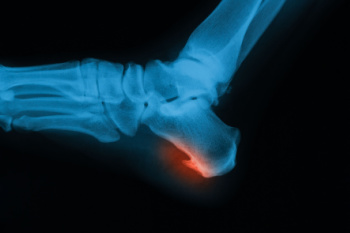

Heel spurs are bony growths that develop on the heel bone due to long-term strain on foot muscles and ligaments. They often form where the plantar fascia connects to the heel, causing discomfort and inflammation. Common causes include repetitive stress, wearing improper footwear, and prolonged standing. Risk factors such as flat feet, obesity, and age can increase the likelihood of developing them. There are two main types. Plantar heel spurs located under the heel and dorsal heel spurs form on the back near the Achilles tendon. Symptoms include sharp pain, tenderness, or stiffness. A podiatrist can diagnose heel spurs through an examination and imaging tests, and provide treatments that reduce pain and improve mobility. If you have heel pain, it is suggested that you schedule a visit with a podiatrist for an accurate diagnosis and treatment.

Heel spurs are formed by calcium deposits on the back of the foot where the heel is. This can also be caused by small fragments of bone breaking off one section of the foot, attaching onto the back of the foot. Heel spurs can also be bone growth on the back of the foot and may grow in the direction of the arch of the foot.

Older individuals usually suffer from heel spurs and pain sometimes intensifies with age. One of the main condition's spurs are related to is plantar fasciitis.

The pain associated with spurs is often because of weight placed on the feet. When someone is walking, their entire weight is concentrated on the feet. Bone spurs then have the tendency to affect other bones and tissues around the foot. As the pain continues, the feet will become tender and sensitive over time.